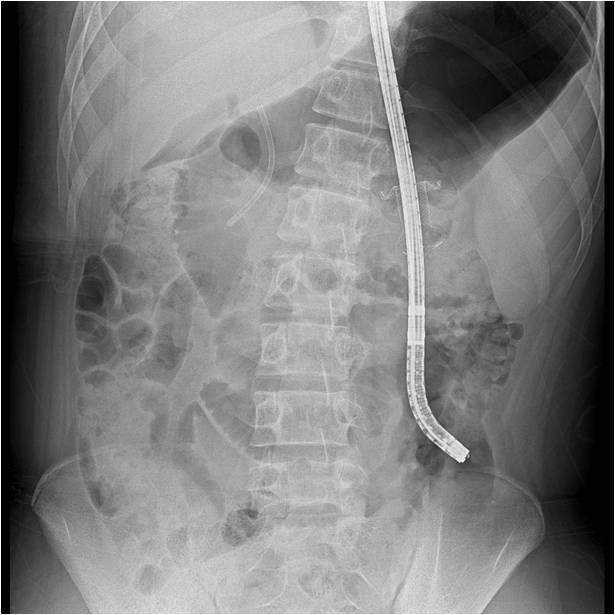

박 교수는 먼저 초음파내시경으로 위와 괴사주머니를 연결하는 통로를 만드는 내강밀착형 스텐트(lumen apposing metal stent)를 삽입했다. 이후 스텐트 내부를 통해 위내시경을 넣어 췌장의 괴사조직을 직접 제거했다. 일반적으로 내시경적 괴사제거술은 평균 5회가량 시행하지만 김 군의 경우 괴사 부위가 워낙 커 17회나 괴사제거술을 시행한 끝에 괴사조직을 완전히 제거할 수 있었다. 이후 두 달간의 치료를 성공적으로 마친 김 군은 처음 병원에 입원할 때보다 체중이 15㎏ 줄었지만 건강한 모습으로 퇴원해 학교생활을 하고 있다.

박 교수는 "경피적 배액술과 최소침습적 수술의 도움 없이 총 17회의 내시경적 괴사제거술만으로 골반강까지 확장된 괴사조직을 치료한 국내 첫 사례"라며 "골반강까지 길고 좁게 형성된 괴사주머니 내부를 풍선으로 확장하면서 괴사제거술을 진행한 경우는 전 세계적으로도 드문데다 천공이 생길 위험성도 매우 높은 고난도 시술에 속한다"고 설명했다.